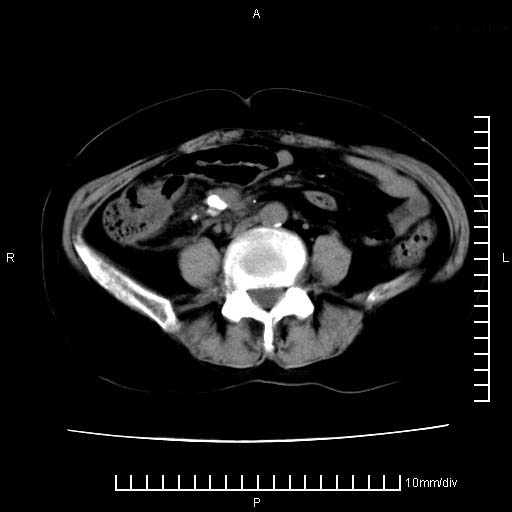

下腹疼痛2月,加重并呕吐2天,下腹压痛,反跳痛。白细胞1万2.

下腹至盆腔较大包块,与邻近肠管关系密切,下腹疼痛2月,加重并呕吐2天,下腹压痛,反跳痛。白细胞1万2.

由于没有做肠道准备很难分清是哪根肠管,但看位置考虑为升结肠回盲部的问题,我首先考虑化脓性阑尾炎,不除外结肠癌合并感染化脓。建议做增强进一步明确。

补充:道格拉斯腔内有积液,且密度较高,显然提示有感染。

盆腔脓肿伴盆腔积液

盆腔脓肿伴积液可能性大。

考虑卵巢恶性肿瘤;盆腔积液。